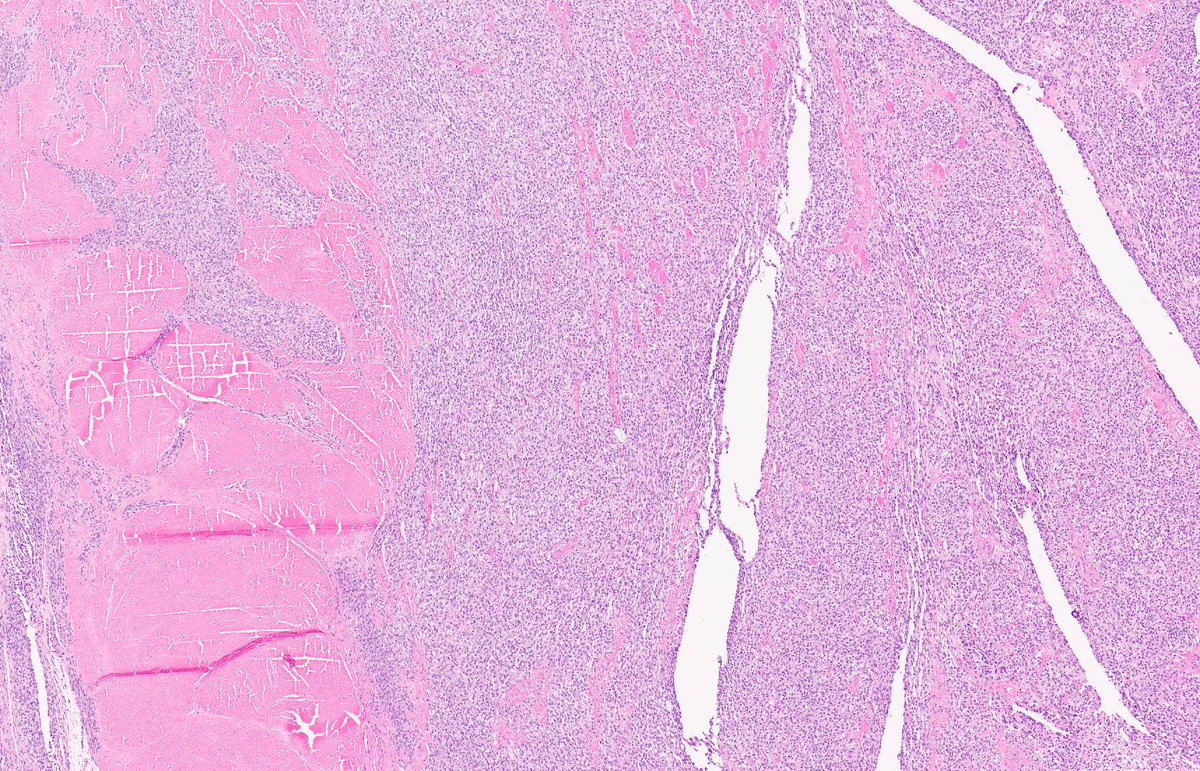

MASSIVE LOCALIZED LYMPHOEDEMA. NB: lobules of mature adipose tissue; expanded interlobular septa; spindle-stellate cells with mild atypia and prominent myxoid background; ectatic lymphatic spaces; MDM2 non-amp; typically occurs in context of morbid obesity (PMID: 9777990).

3

12

30